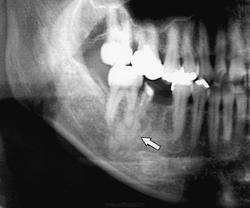

Дисплазия цементо - костная.

Продолжение.